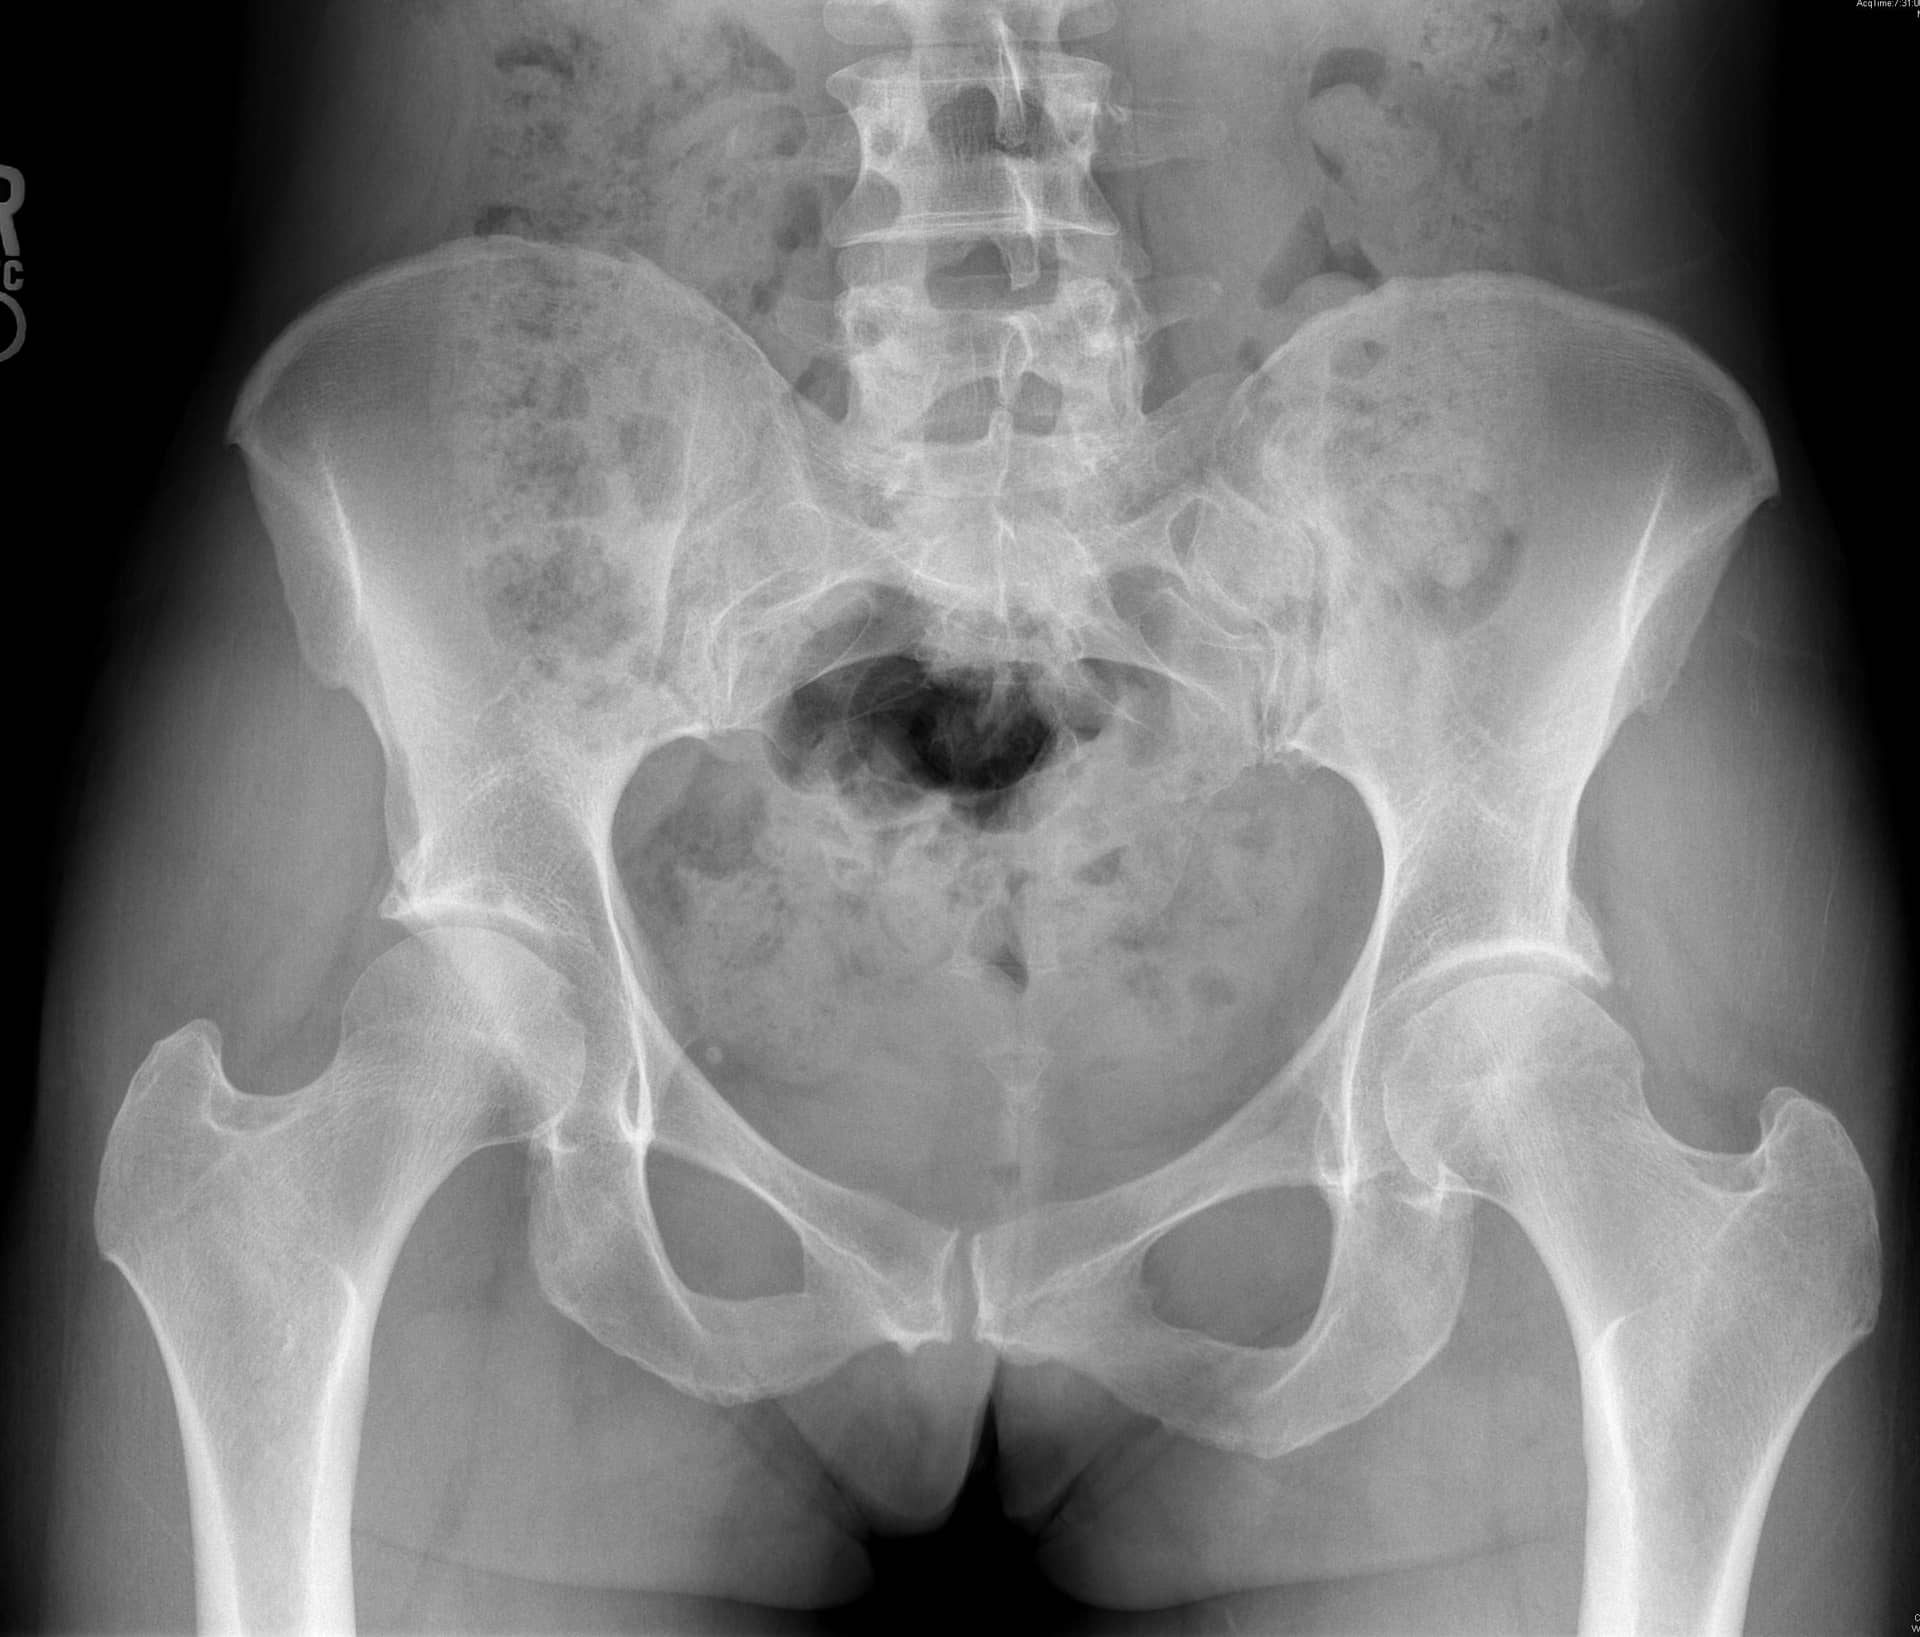

एक एपी श्रोणि दृश्य प्रभावित और अप्रभावित फेमोरा की तुलना की अनुमति देता है। यह सुनिश्चित करने के लिए समरूपता का आकलन करें कि एक सच्चा एपी दृश्य कैप्चर किया गया है। इसका आकलन यह जांचकर किया जा सकता है कि कोक्सीक्स सिम्फिसिस पबिस को ओवरलैप करता है, जिसमें दो संरचनाओं के बीच 2 सेमी से अधिक अलगाव नहीं होता है। संयुक्त स्थान में कमी और अपक्षयी परिवर्तनों के लिए संयुक्त का मूल्यांकन किया जाना चाहिए। अप्रभावित पक्ष के साथ एंटेरोलेटरल गर्दन समोच्च की तुलना करें। बेहतर गर्दन की शंकु की कमी सिर-गर्दन ऑफसेट को कम करने का संकेत देती है। एंटेरोसुपीरियर या पूर्ववर्ती सिर की सपाट या बढ़ी हुई त्रिज्या एक गोलाकार सिर को इंगित करती है। कई मापों का विश्लेषण किया जा सकता है:

- पार्श्व केंद्र एज कोण: ऊरु सिर के केंद्र से खींची गई एक ऊर्ध्वाधर रेखा द्वारा बनाया गया कोण और पार्श्व रिम से सिर के केंद्र तक खींची गई रेखा। 20 डिग्री से कम कोण डिस्प्लेसिया को इंगित करता है।

- एसिटैबुलर इंडेक्स: एसिटैबुलर छत या सॉर्सिल द्वारा बनाया गया कोण। 10 डिग्री से अधिक का कोण डिस्प्लेसिया को इंगित करता है।

- एसिटैबुलर संस्करण: एसिटेबुलर रिम के पूर्ववर्ती और पीछे के अनुमानों के साथ एंटेरोलेटरल एसिटेबुलर किनारे से रेखाओं का पता लगाता है। एक पूर्ववर्ती दीवार जो पीछे की दीवार ("पीछे की दीवार का संकेत") की तुलना में अधिक पार्श्व है, रेट्रोवर्सन को इंगित करती है। एक पूर्ववर्ती दीवार जो पीछे की दीवार ("क्रॉस-ओवर साइन") को पार करती है, पूर्ववर्ती रिम और सापेक्ष रेट्रोवर्सन पर बोनी अधिकता को इंगित करती है।

- एफएआई के मूल्यांकन के लिए एक क्रॉस-टेबल पार्श्व दृश्य महत्वपूर्ण है, जिससे एंटेरोलेटरल फेमोरल गर्दन का दृश्य देखने की अनुमति मिलती है।

- अल्फा-कोण: ऊरु गर्दन की मध्य रेखा के साथ एक रेखा और ऊरु सिर के केंद्र से उस बिंदु तक एक रेखा के बीच बनता है जहां अतिरिक्त हड्डी सामान्य ऊरु सिर स्फेरिसिटी से विचलित होती है। 60 डिग्री से अधिक का कोण एफएआई को इंगित करता है।

- सिर-गर्दन ऑफसेट: ऊरु गर्दन के अनुदैर्ध्य अक्ष को विभाजित करने वाली रेखा से शुरू करें। एक समानांतर रेखा खींचें जो ऊरु गर्दन के पूर्ववर्ती पहलू के लिए स्पर्शरेखीय है और पूर्ववर्ती ऊरु सिर के समानांतर रेखा स्पर्शरेखा की दूरी को मापें। सामान्य दूरी 9 मिमी से अधिक है या सिर के व्यास का अनुपात 0.17 से अधिक है।

एमआरआई और सीटी का उपयोग एसिटाबुलम और समीपस्थ फीमर के आगे के मूल्यांकन के लिए किया जा सकता है। ये अध्ययन एसिटेबुलर संस्करण और नरम ऊतक के प्रभाव का बेहतर मूल्यांकन प्रदान कर सकते हैं या प्रीऑपरेटिव प्लानिंग में मदद कर सकते हैं। एमआर आर्थ्रोग्राम ऊरु गर्दन के कैम घाव के निदान में भी सहायता कर सकता है, लैब्रम या उपास्थि का आकलन कर सकता है। रेडियल अनुक्रमण सबसे अच्छा है, एक असामान्य लैब्रम कुंद दिखाई देगा या इसके आधार पर बढ़े हुए संकेत के साथ दिखाई देगा। 3, 4 एसिटैबुलर रेट्रोवर्जन के कारण पिंसर का प्रभाव, शुरू में लैब्रल विफलता दिखाएगा, जिसके बाद एक कॉन्ट्राकूप तंत्र के परिणामस्वरूप पोस्टरोहीन एसिटेबुलर कार्टिलेज में छोटे, पतले घाव होंगे। 5 इसे क्रॉस-ओवर संकेत, पीछे की दीवार के संकेत, या रेडियोग्राफ़ पर एक नकारात्मक खट्टा कोण के साथ पुन: प्रदर्शित किया जा सकता है। एमआरआई में कुंद लैब्रम, ऊरु गर्दन पर चुंबन घाव, पीछे के एसिटेबुलर कार्टिलेज का घिसना, या एक रेट्रोवर्टेड एसिटाबुलम प्रदर्शित होगा। ऊरु गर्दन के घावों के कारण कैम का प्रभाव, उपास्थि की प्रारंभिक विफलता को दर्शाता है, जिसके बाद लैब्रल फट जाता है। पार्श्व एक्स-रे पर सिर-गर्दन ऑफसेट में कमी, ऊरु गर्दन पर अतिरिक्त हड्डी की आकृति और बढ़े हुए अल्फा-कोण का आकलन निदान में सहायता कर सकता है। एमआरआई पर लैब्रम अपने आधार पर फटने का प्रदर्शन कर सकता है, एक असामान्य ऊरु सिर-गर्दन समोच्च स्पष्ट हो सकता है, या उपास्थि प्रदूषण स्पष्ट हो सकता है। रोगी 80% मामलों में कैम और पिंसर दोनों के साथ पेश होंगे, हालांकि एक रूप आमतौर पर प्रमुख होता है। 2